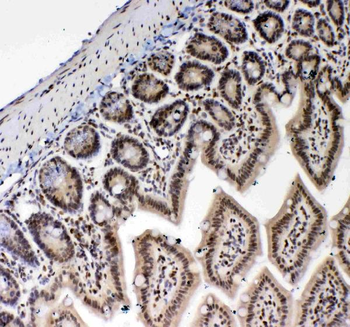

10 μg, 100 μg - Anti-CD44 Antibody [orb402179]

ELISA, FC, ICC, IF, IHC, IHC-Fr, WB

Human, Mouse, Rat

Rabbit

Polyclonal

Unconjugated

10 μg, 100 μg - Anti-PRDM1/Blimp1 Antibody [orb402200]